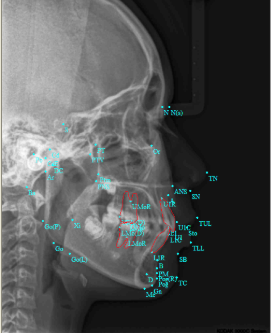

牙弓对脸型的影响:↓